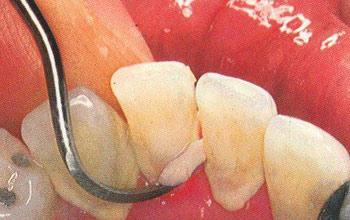

牙周病的病因比較複雜,可分為口腔衛生不良、牙齒排列錯亂以及全身性因素3個方面,但3方面的因素都不是孤立存在的。牙菌斑是本病主要致病的因素,牙菌斑中絕大多數細菌為口腔正常菌叢,僅少數細菌與牙周病的發生、發展密切相關,從而導致牙周病的產生。

5、保持口腔清潔。要記得每天的早晨和晚上都應該刷牙,最好堅持用溫水,而且很多人不知道的是晚上睡覺之前的刷牙比早晨醒來的刷牙更為重要。此外,一日三餐後要用清水漱口,漱口時要借用水的衝力儘量將牙縫中的食物殘渣清除。如嵌得很緊,也可用牙籤除掉。應定期去醫院除去牙面上的結石,以防止牙周炎的發生。